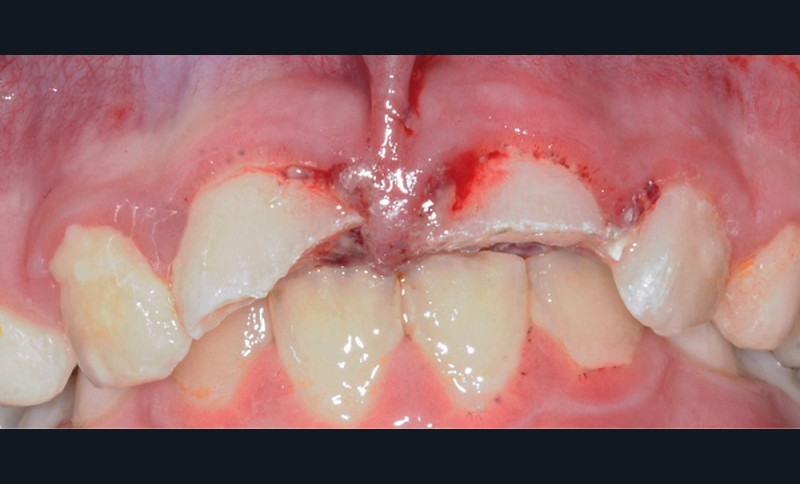

- une plaie au niveau du frein labial supérieur ;

- une fracture corono-radiculaire avec effraction pulpaire de 11 et 21 (fig. 1 et 2) ;

- une subluxation de 11 et 21 (saignements sulculaires).